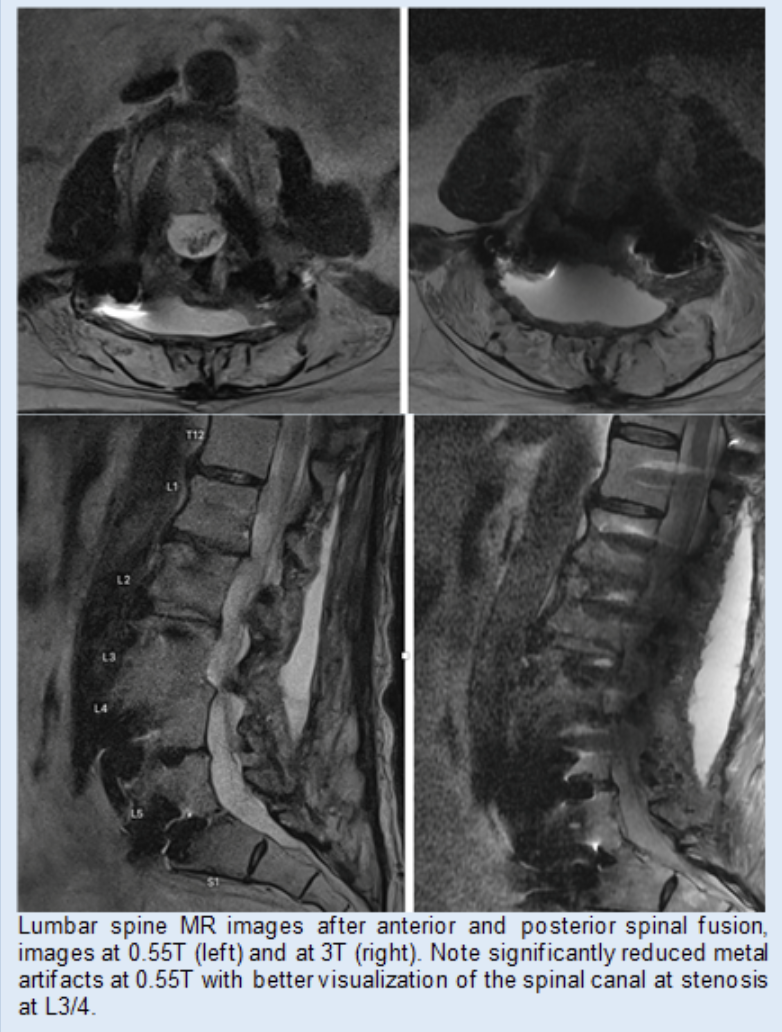

The Clinical and Translational MSK Imaging group (CTMI) uses standard and novel imaging techniques to study abnormalities of the musculoskeletal system. Our focus is on imaging biomarkers in osteoarthritis; the team has developed quantitative and semi-quantitative measurement tools to assess and monitor disease severity. These include Whole-Organ Magnetic Resonance Imaging Scores (WORMS) of the knee, composite scores to measure knee joint synovitis, and the Scoring Hip Osteoarthritis with MRI (SHOMRI) system to study the hip. In addition, artificial intelligence-based tools to measure muscle volume and fat infiltration, periarticular adipose tissue, and synovitis volume have been developed. Recently, we also investigated novel MR imaging techniques to reduce metal artifacts, low field MRI at 0.55T, and CT-like MR imaging techniques.